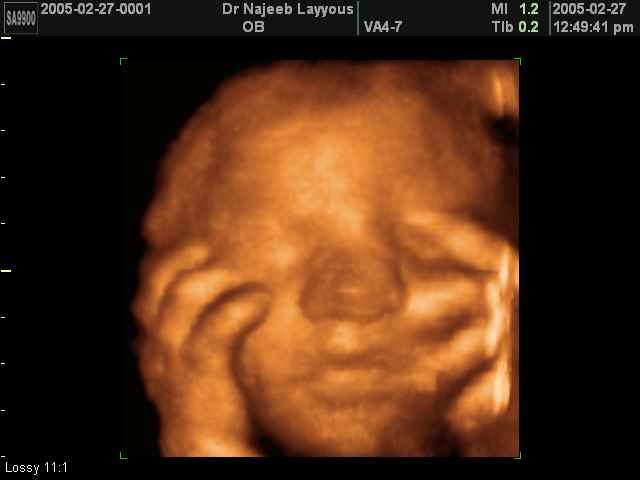

3D Ultrasound Scan Photos of Fetal Limbs | Dr N Layyous

3D Fetal Limbs Ultrasound Scan Photos